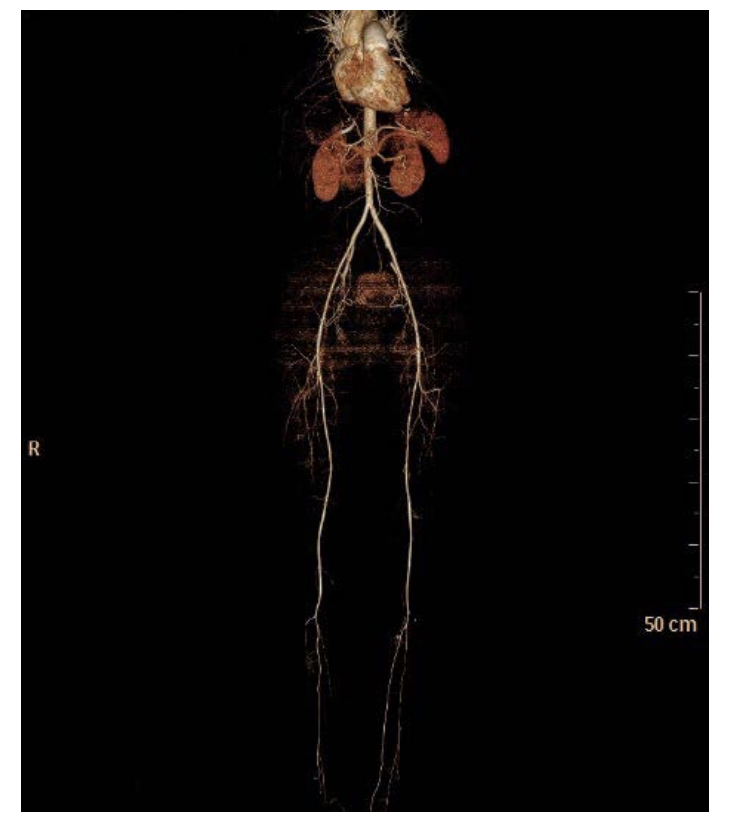

The patient was anticoagulated with heparin from the moment of presentation in the emergency room and continued postoperatively on warfarin. She needed oxygen by nasal canula as she was hypoxic at room air. The cardiologist, cardiac surgeon, and pulmonary physician recommended her to continue on anticoagulation. The patient was discharged from the hospital on warfarin and home oxygenator and followed up in the outpatient clinic. There was a dramatic clinical improvement, as she was removed from the oxygenator and walking around normally. A follow up CT angiography of the lower limbs showed well perfused limbs (Figure 3).